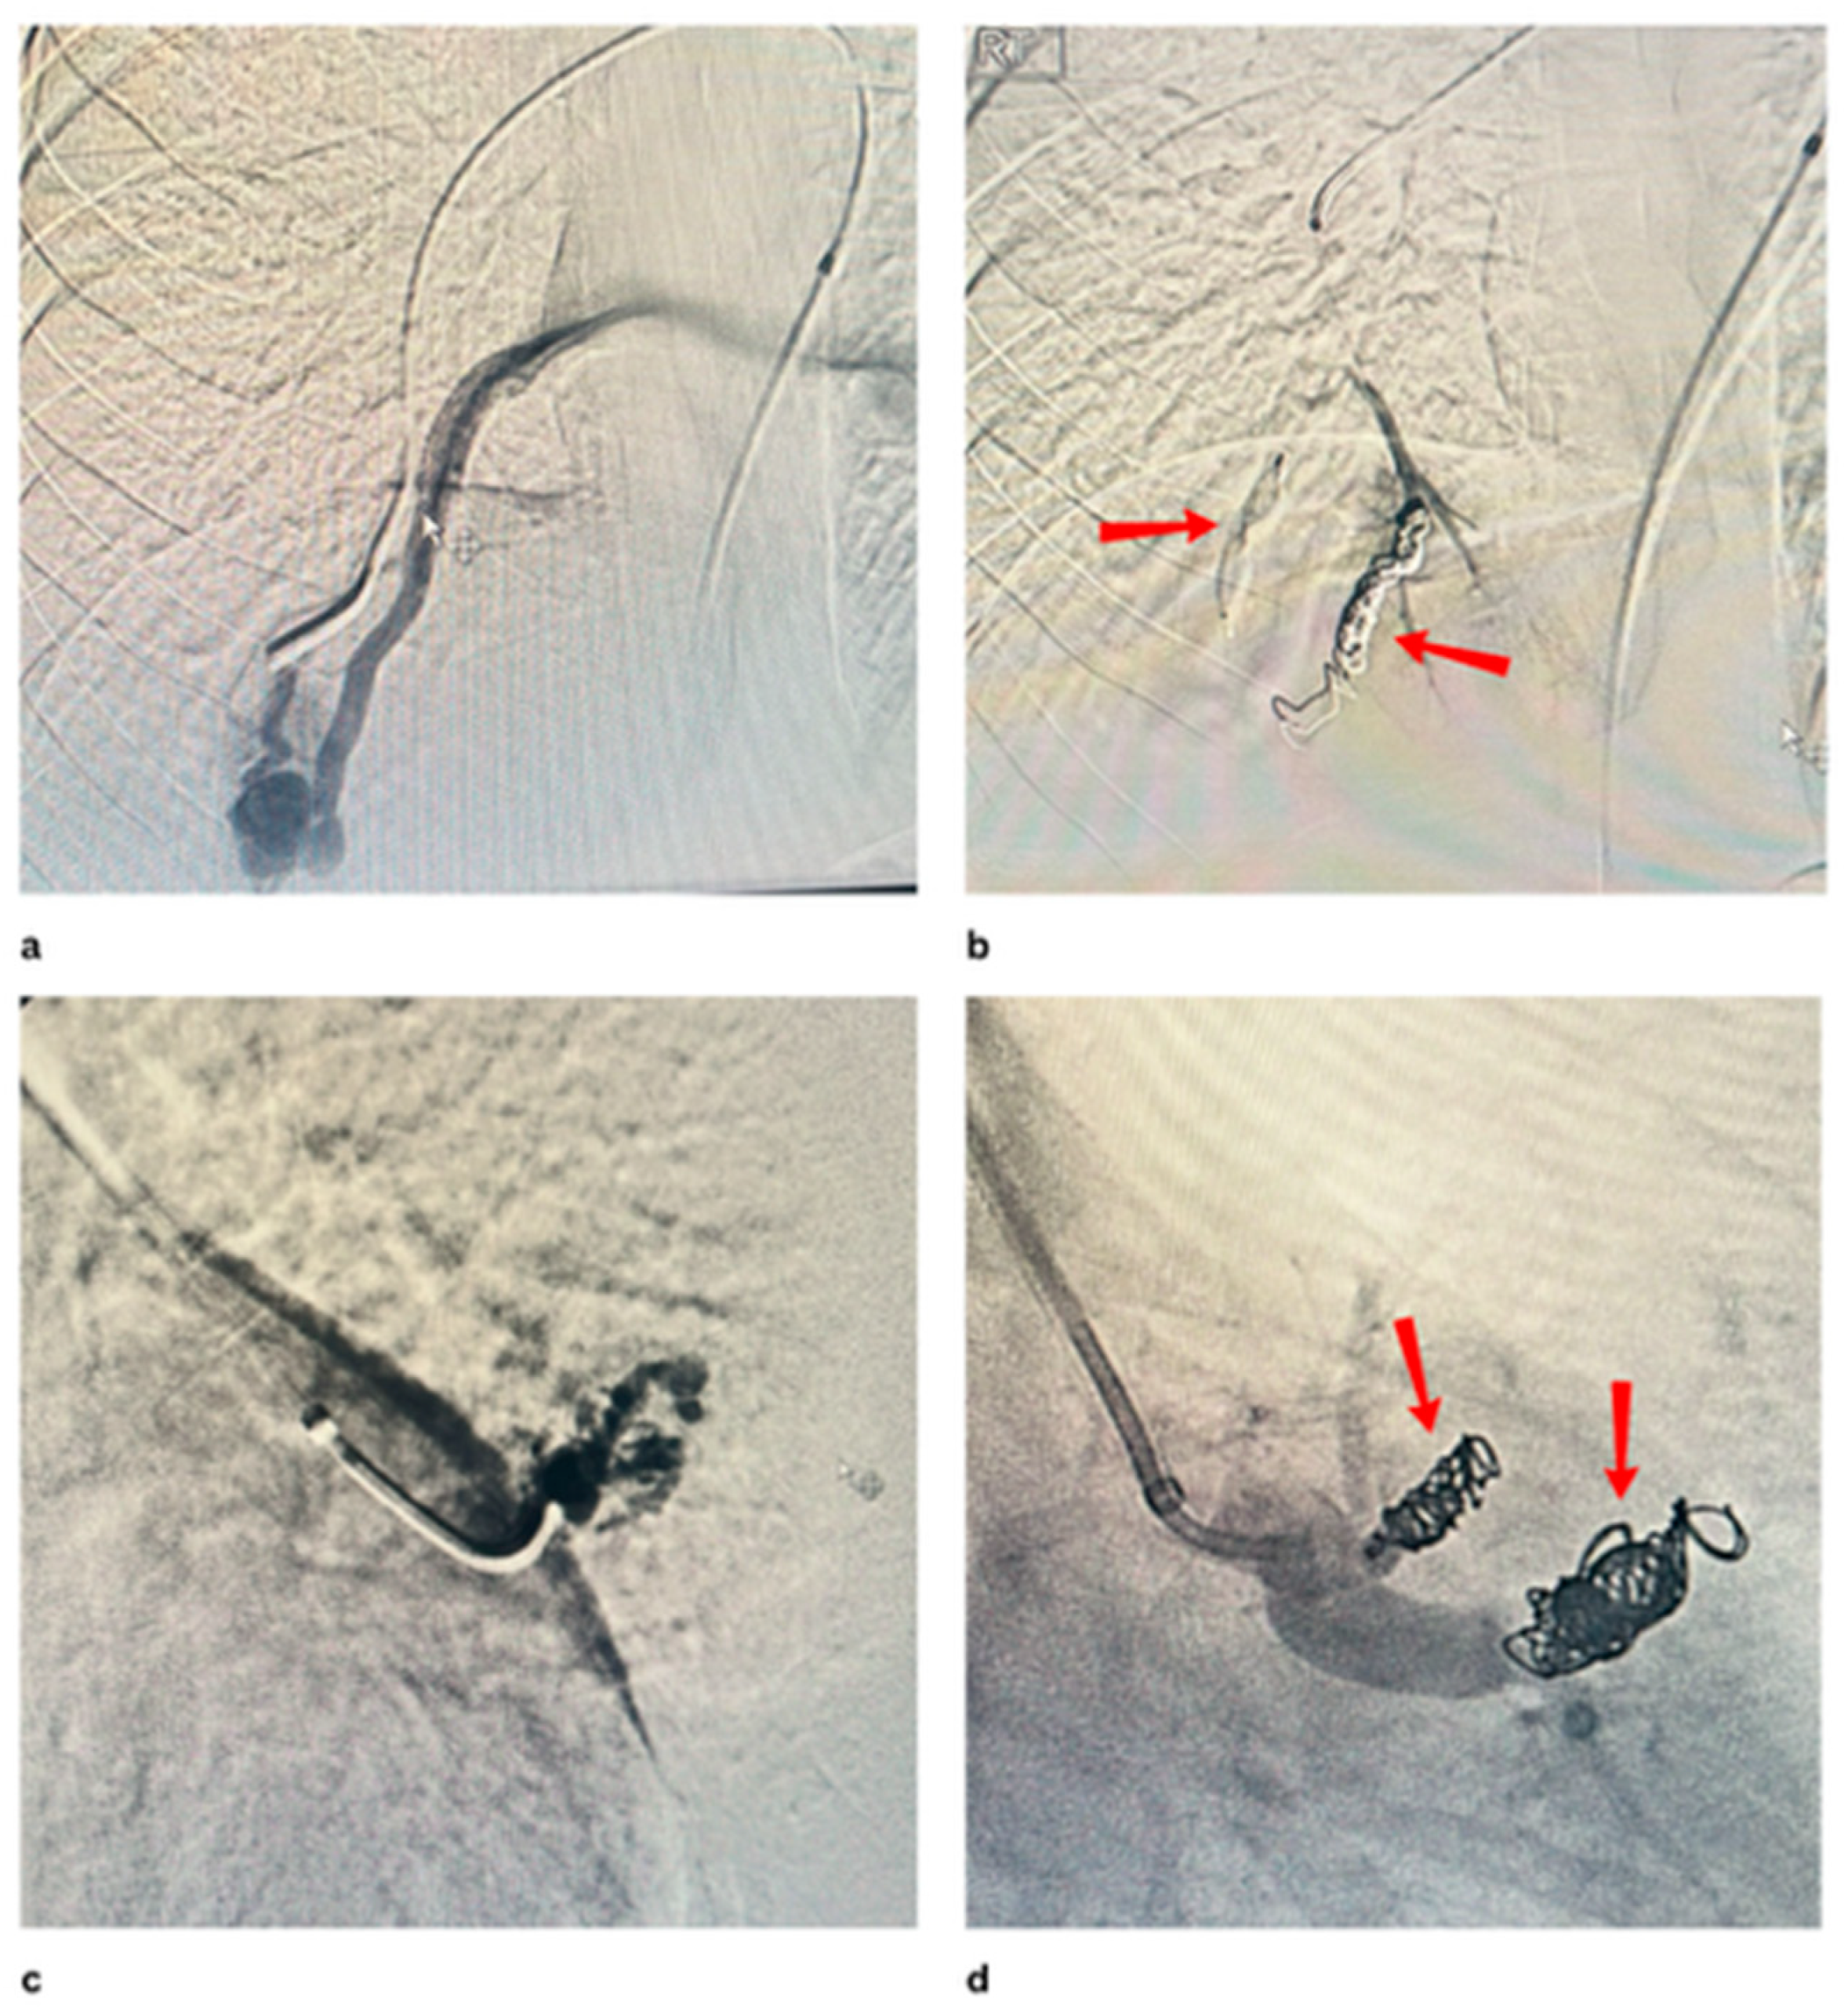

- Chu, H.H.; Kim, G.H.; Gwon, D.I. An Alternative Endovascular Technique for Treatment of Pulmonary Arteriovenous Malformation: Microballoon-occluded Transcatheter Embolization Using n-butyl-2-cyanoacrylate. Cardiovasc. Interv. Radiol. 2024, 47, 1109–1116. [Google Scholar] [CrossRef]